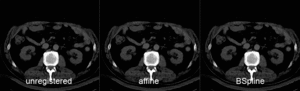

Registration Results (click to enlarge)

unregistered MRI & CT

after linear (affine) registration

after nonrigid registration

comparing kidney alignment at different registration stages